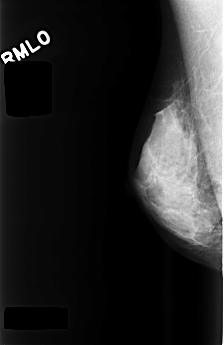

C_0477_1.RIGHT_MLO

RIGHT_CC LINES 4520 PIXELS_PER_LINE 2880 BITS_PER_PIXEL 12 RESOLUTION 50 NON_OVERLAY

RIGHT_MLO LINES 4480 PIXELS_PER_LINE 2912 BITS_PER_PIXEL 12 RESOLUTION 50 NON_OVERLAY